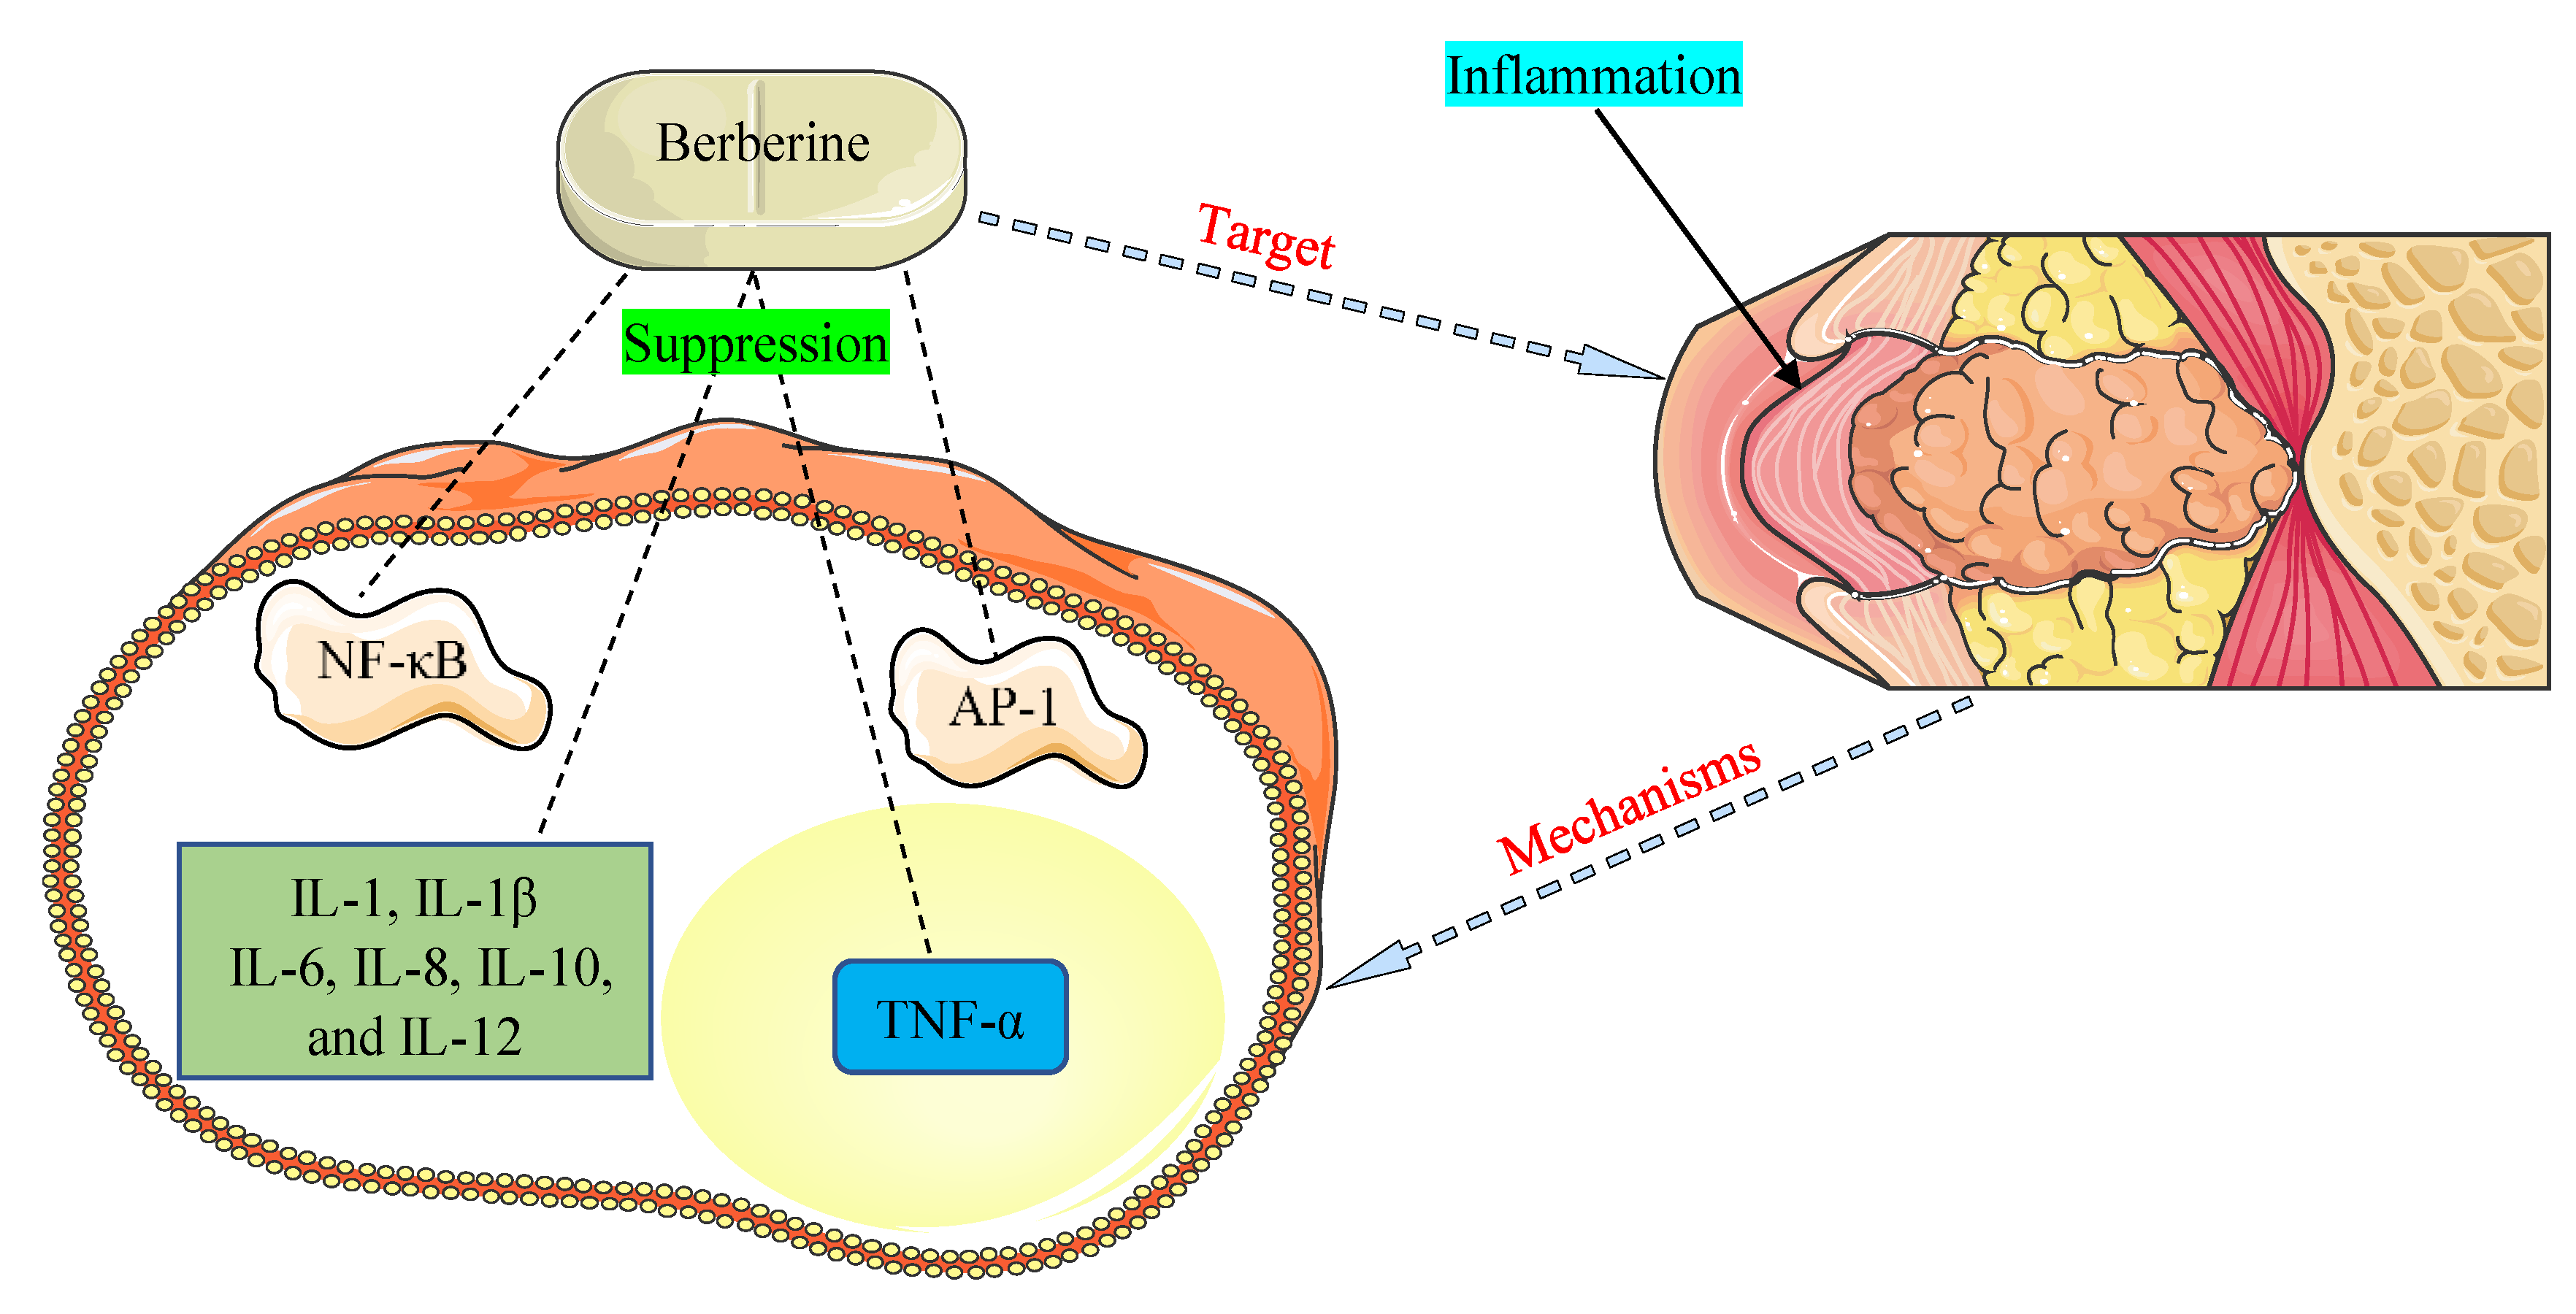

Медицинские снимки и изображения опоясывающего герпес вируса

Раздел: Фотодневник открытий